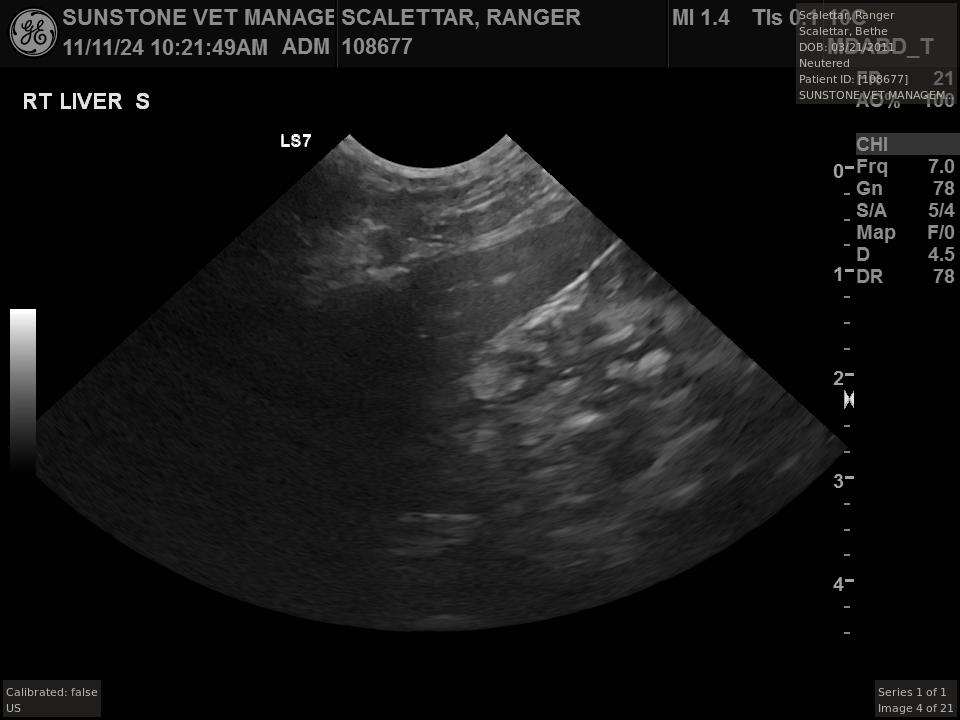

Veterinary ultrasound examinations of the thorax and/or abdomen typically include a number

of views selected to assess the health and function of internal organs. Unlike with radiography,

the images do not include the lungs because ultrasound reflects off the outer boundaries of the

lungs, making it difficult to see inner structures.

The veterinarian generated a series of images showing different organs and substructures by

changing the position and orientation of the ultrasound transducer. The images were collected

in a defined order, which is repeated from patient to patient, ensuring that nothing is missed. In

Ranger's case, the sonographer collected about twenty images during an examination that

lasted about fifteen minutes.

The sonographer stated that Ranger's ultrasound images were largely normal for an older cat. In particular, they show changes in the kidneys that are commonly noted in geriatric cats and that reflect a risk for the development of chronic kidney disease. However, the images did not show any significant abnormalities in Ranger's stomach, intestines, and associated lymph nodes. Nonetheless, the results did not rule out recurrence of Ranger's small cell lymphoma.